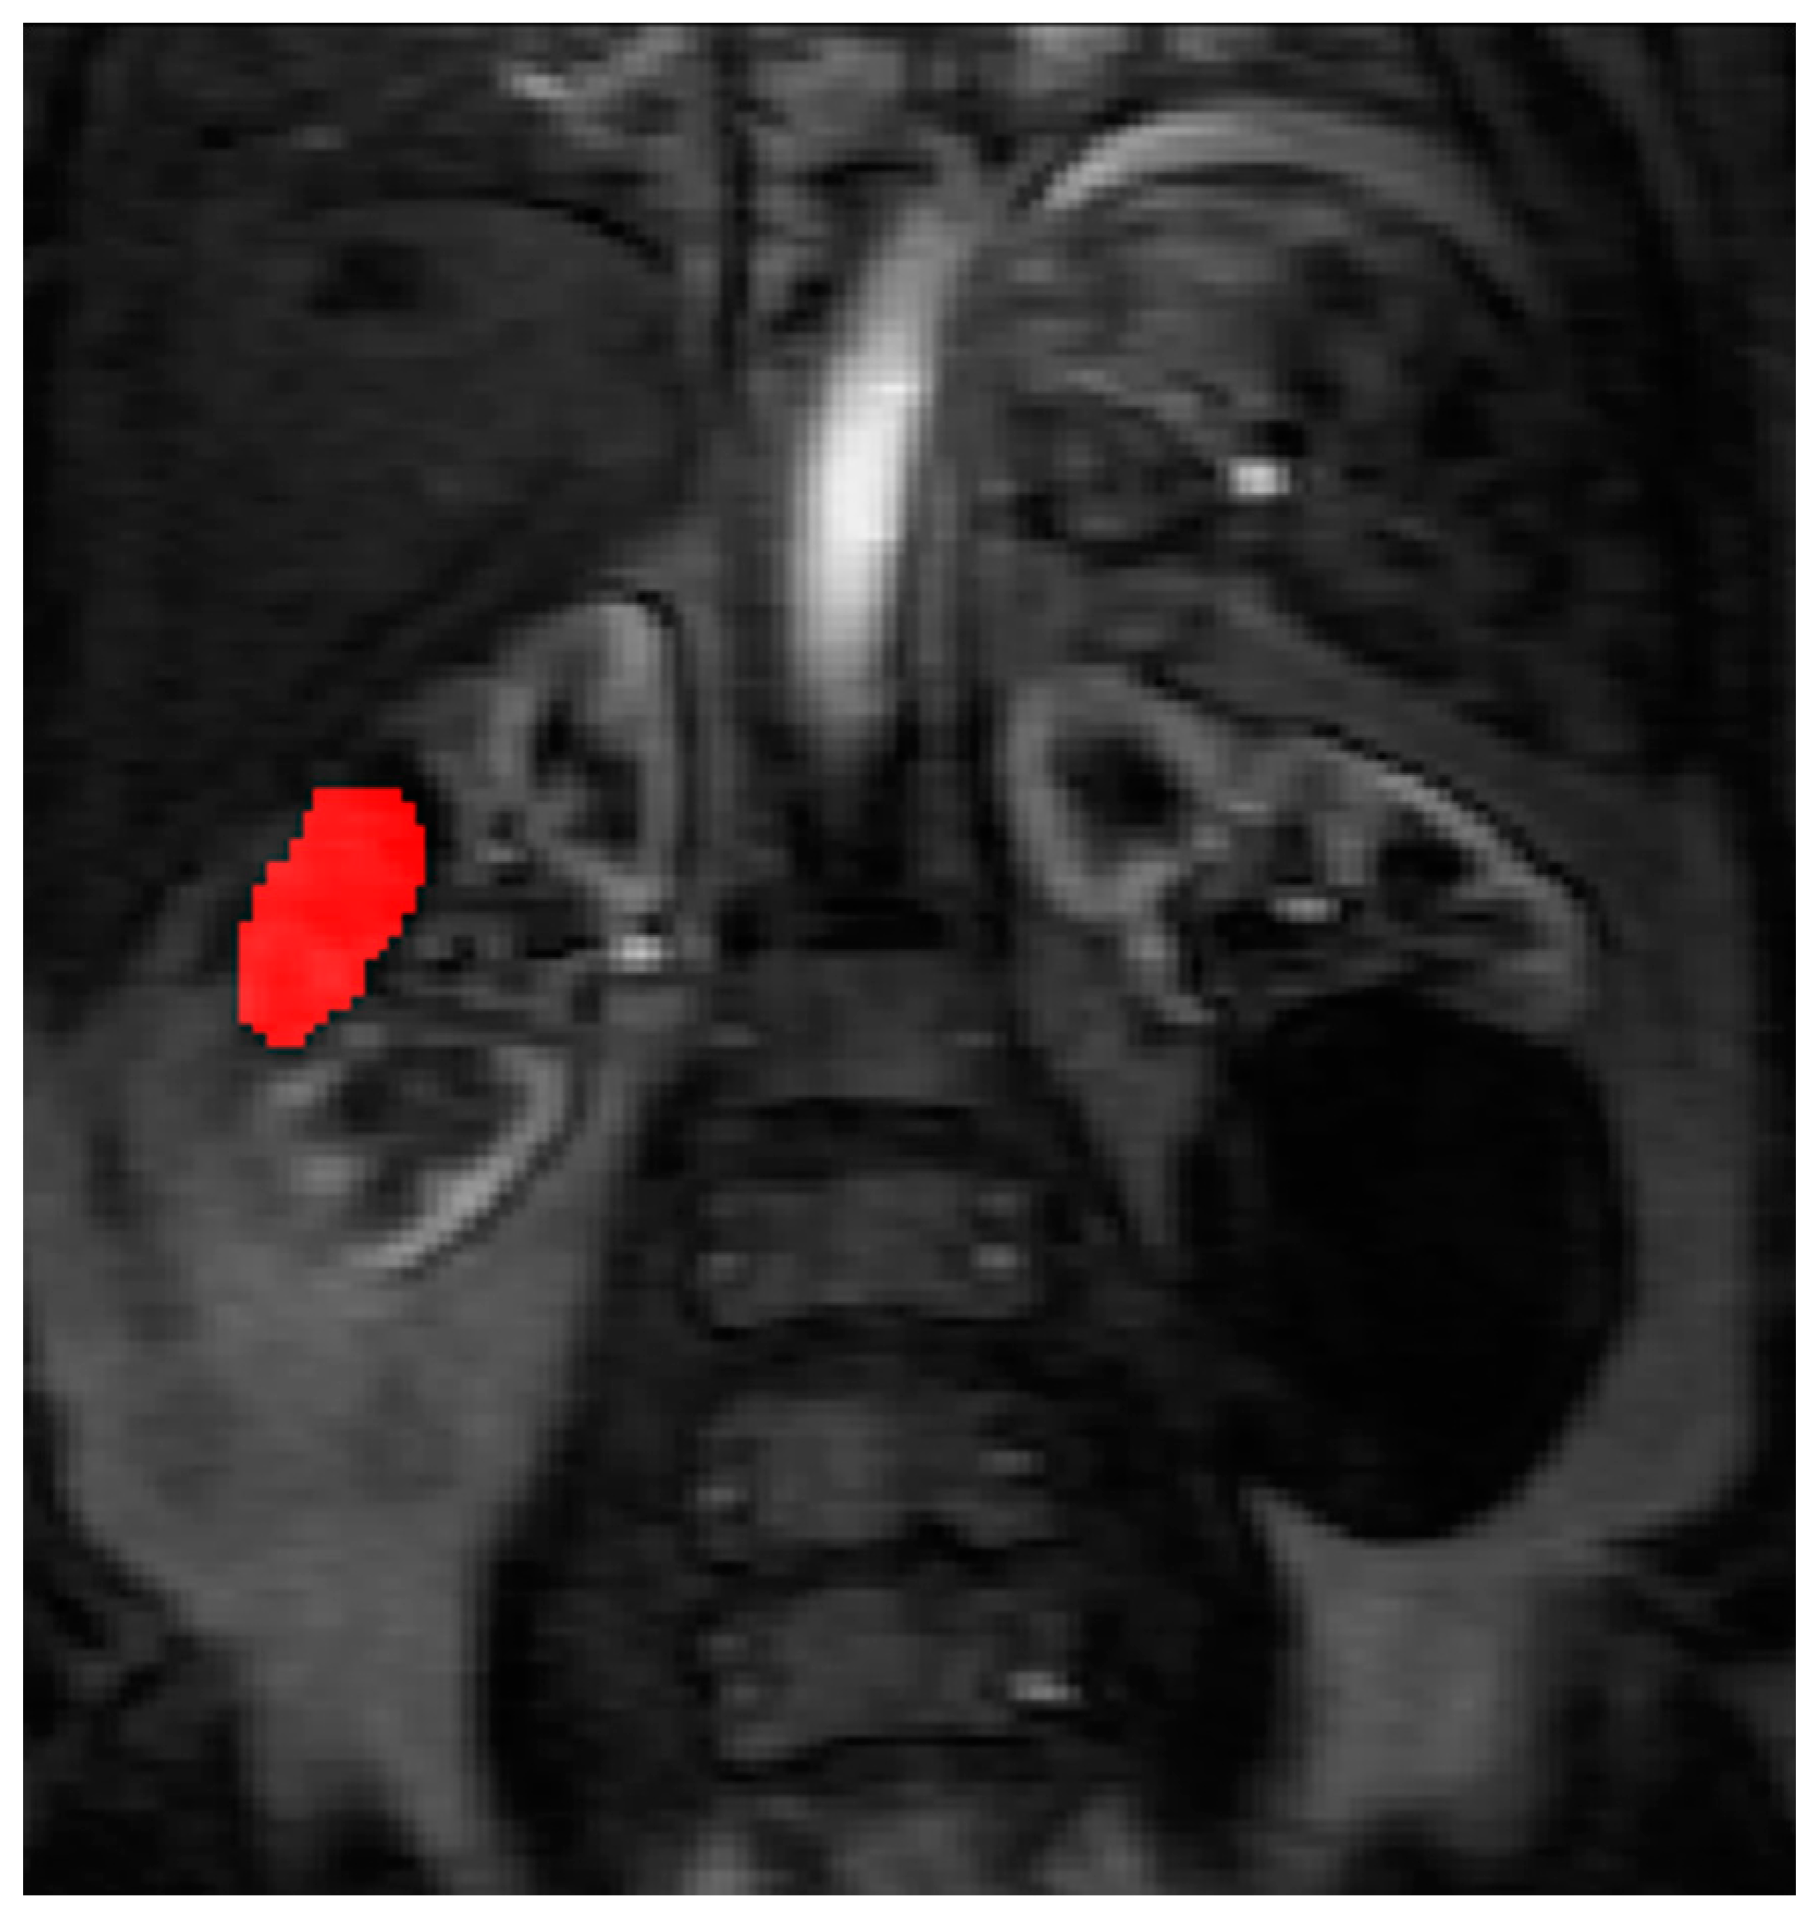

Contrast agent concentration-time curves were approximated using relative change in signal (compared to baseline) against time [13]. To assist in identifying the tumour and drawing the ROI, a map of maximum contrast agent concentration was generated. Using the map, ROIs were drawn to encompass the renal tumour pre RFA (Figure 3) and the whole zone of ablation post RFA (Figure 4).

The pre RFA renal tumour and post RFA zone of ablation in every patient were saved and anonymized within the same dataset. Pre RFA, the ROI outlined the bright area which represents the enhancing renal tumour. In this cohort, some of the tumours had a cystic or necrotic component, but only the solid components were included in the ROIs. Post RFA, the ROI outlined the whole zone of ablation which is typically larger than the tumour to allow for the ‘surgical’ margin, this is the dark area on images that represents ‘dead’ renal tumour. If there is any bright area within the zone of ablation, this typically suggests area of enhancement and indicates that there is a viable renal tumour and this would be included with the ROI. This process was repeated for every slice containing pre RFA tumour and the post RFA zone of ablation. The regions for each slice were combined giving a volume of interest that covered the perfused renal tumour in the DCE dataset. This was then analyzed to extract concentration-time curves for the renal tumour before treatment and zone of ablation after treatment (Figure 5). The maximum slope of the tumour curve and the peak value of the AIF were determined.

Figure 4. The ROI is drawn on the maximum concentration map generated by PMI software after radiofrequency ablation treatment.